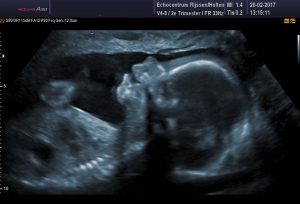

13 weken echo (ETSEO)

Deze echo wordt ook wel eerste trimester structureel echoscopisch onderzoek genoemd (ETSEO) en valt onder prenatale screening. Indien je deze echo wenst wordt deze tussen 12+3 weken en 14+3 weken zwangerschap verricht. Het betreft een echo waarbij het kindje wordt gescreend op lichamelijke afwijkingen.